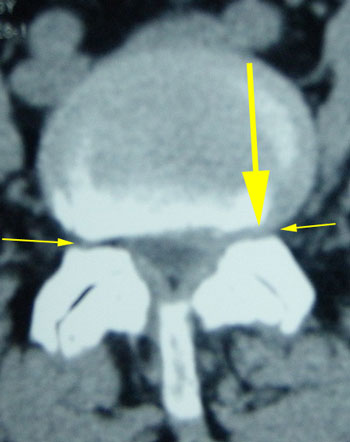

The new MRI was NORMAL. The previously reported large L4-5 disc was completely resorbed. (see picture below)

e2c5e2ef-7ecb-4d25-8377_med       c206d782-08a6-42f7-a45b_med